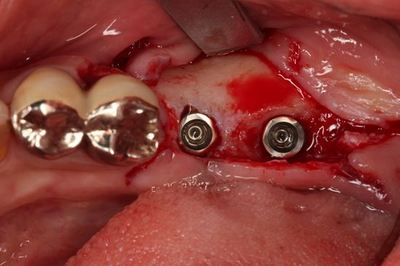

![]()

実際のおくちのミラー像です。

過去の金属治療によるメタルタトゥーがありますので

今回のオペ時に除去します。

となりの金属の連結冠も今後除去します。